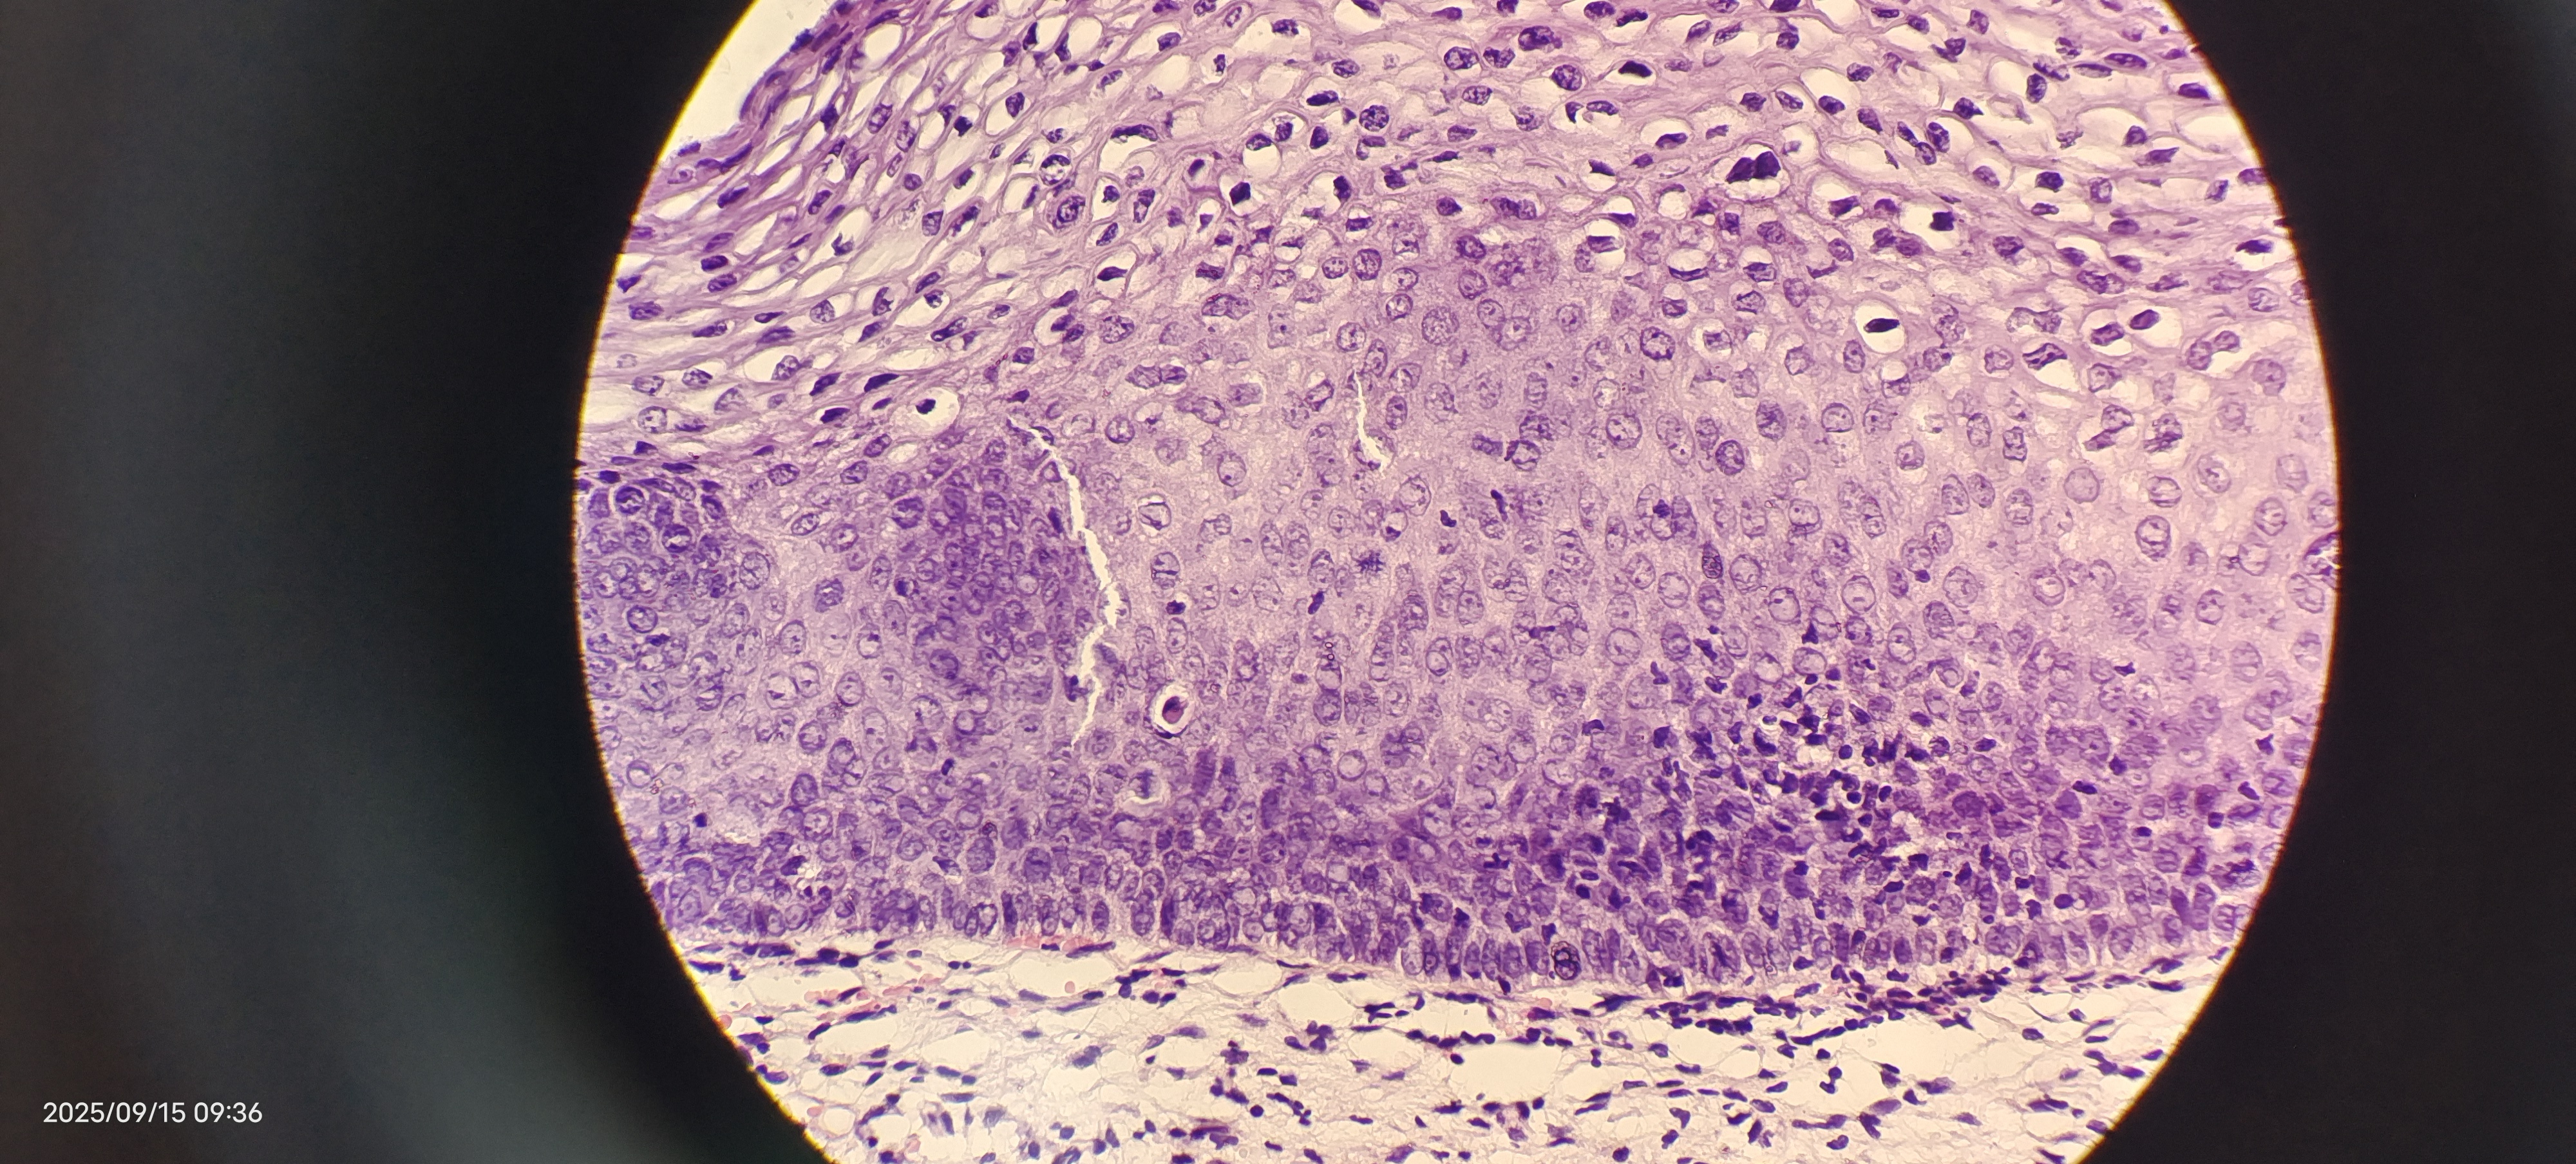

够CIN2级吗

性别

女

年龄

39岁

临床诊断

一般病史

细胞学低级别

标本名称

宫颈活检

大体所见

无

39岁,细胞学低级别 ,最后两张为KI67和P16

图1

图2

图3

图4

图5

CIN1

支持。